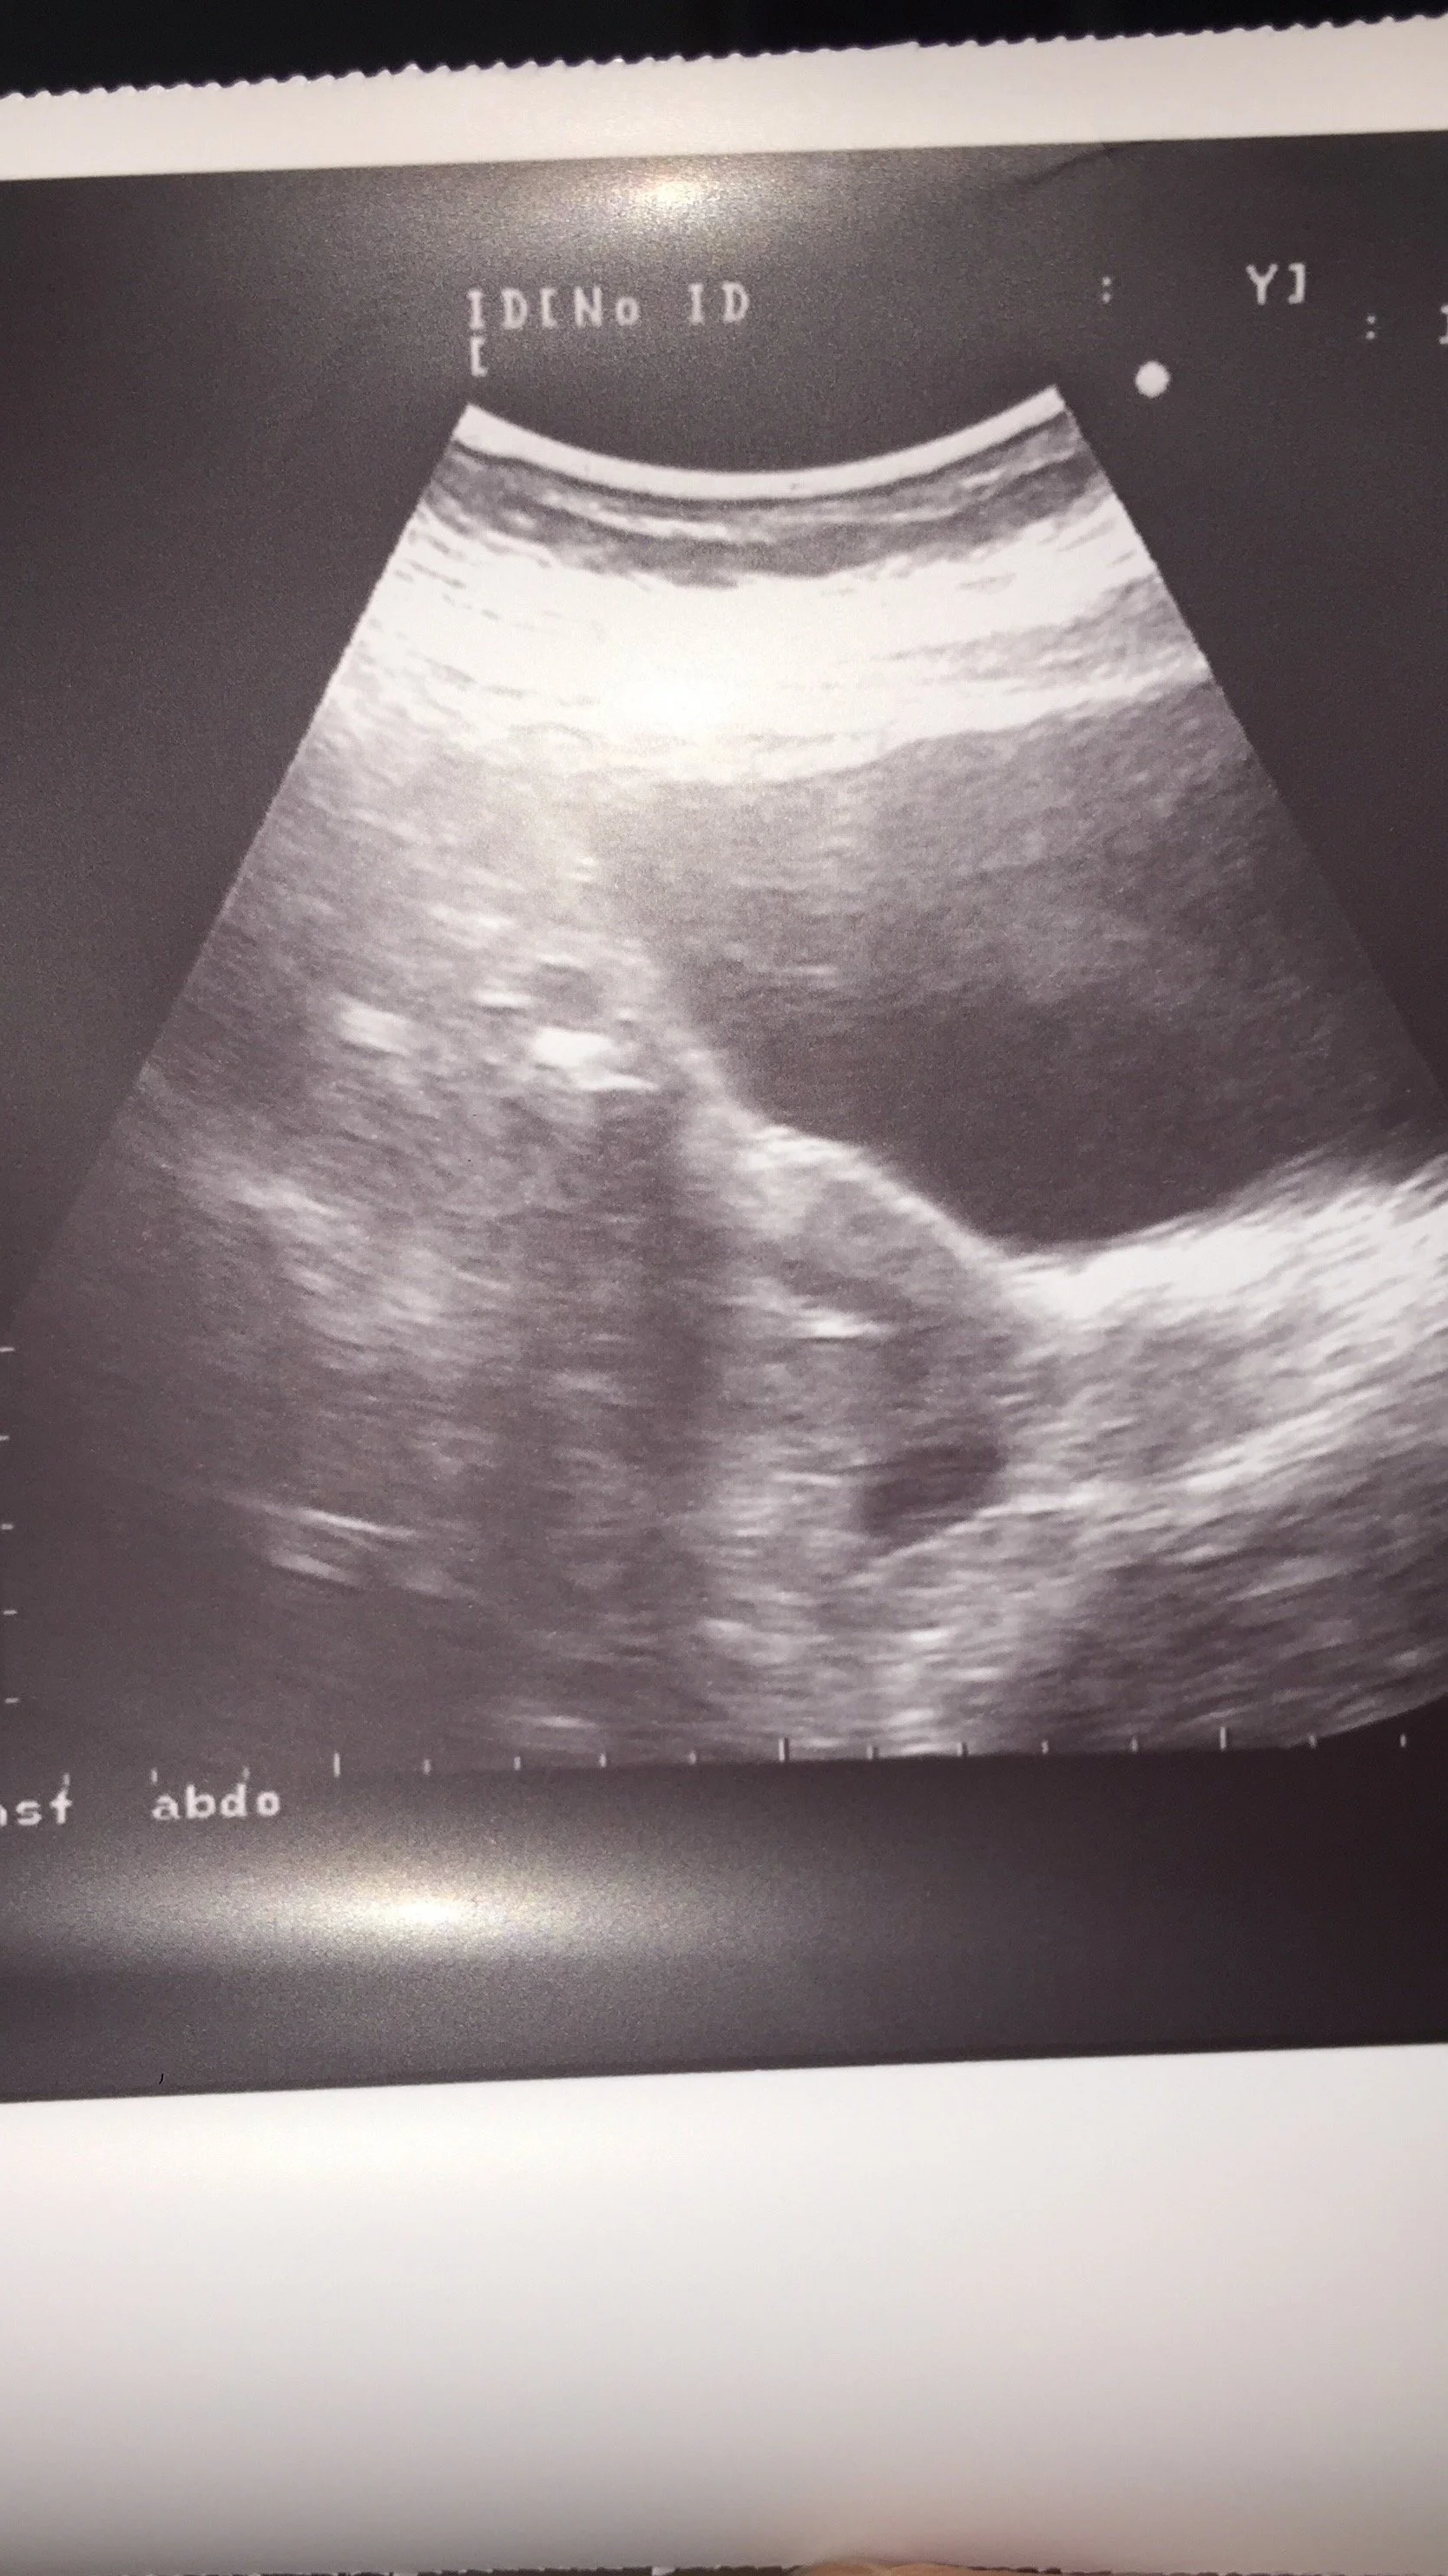

J'ai connu l’univers froid de la PMA, les FIV, le double don, le parcours de l'adoption, l'hystérectomie. Des années à espérer, à me battre, à traverser des deuils successifs — celui des tentatives, celui du projet biologique, celui d'une certaine image de moi-même. Le deuil de la maternité, finalement.